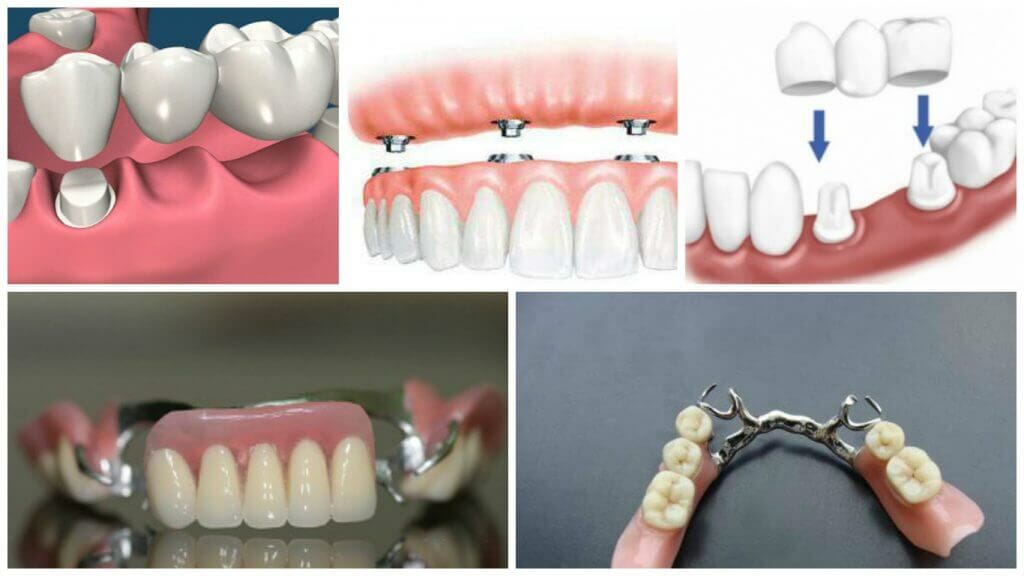

Современные методы протезирования зубов: Рекомендации и советы